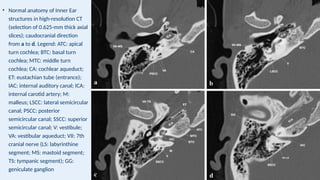

• Normal anatomy of Inner Ear

structures in high-resolution CT

(selection of 0.625-mm thick axial

slices); caudocranial direction

from a to d. Legend: ATC: apical

turn cochlea; BTC: basal turn

cochlea; MTC: middle turn

cochlea; CA: cochlear aqueduct;

ET: eustachian tube (entrance);

IAC: internal auditory canal; ICA:

internal carotid artery; M:

malleus; LSCC: lateral semicircular

canal; PSCC: posterior

semicircular canal; SSCC: superior

semicircular canal; V: vestibule;

VA: vestibular aqueduct; VII: 7th

cranial nerve (LS: labyrinthine

segment; MS: mastoid segment;

TS: tympanic segment); GG:

geniculate ganglion

• Normal anatomyof Inner Ear structures in high-resolution CT (selection of 0.625-mm thick axial slices); caudocranial direction from a to d. Legend: ATC: apical turn cochlea; BTC: basal turn cochlea; MTC: middle turn cochlea; CA: cochlear aqueduct; ET: eustachian tube (entrance); IAC: internal auditory canal; ICA: internal carotid artery; M: malleus; LSCC: lateral semicircular canal; PSCC: posterior semicircular canal; SSCC: superior semicircular canal; V: vestibule; VA: vestibular aqueduct; VII: 7th cranial nerve (LS: labyrinthine segment; MS: mastoid segment; TS: tympanic segment); GG: geniculate ganglion